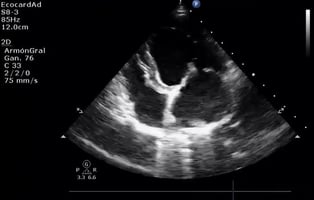

Interactive heart model launched to support client conversations on cardiac disease

Dechra has launched an interactive 4D heart model to enable vets to visually demonstrate the structu...